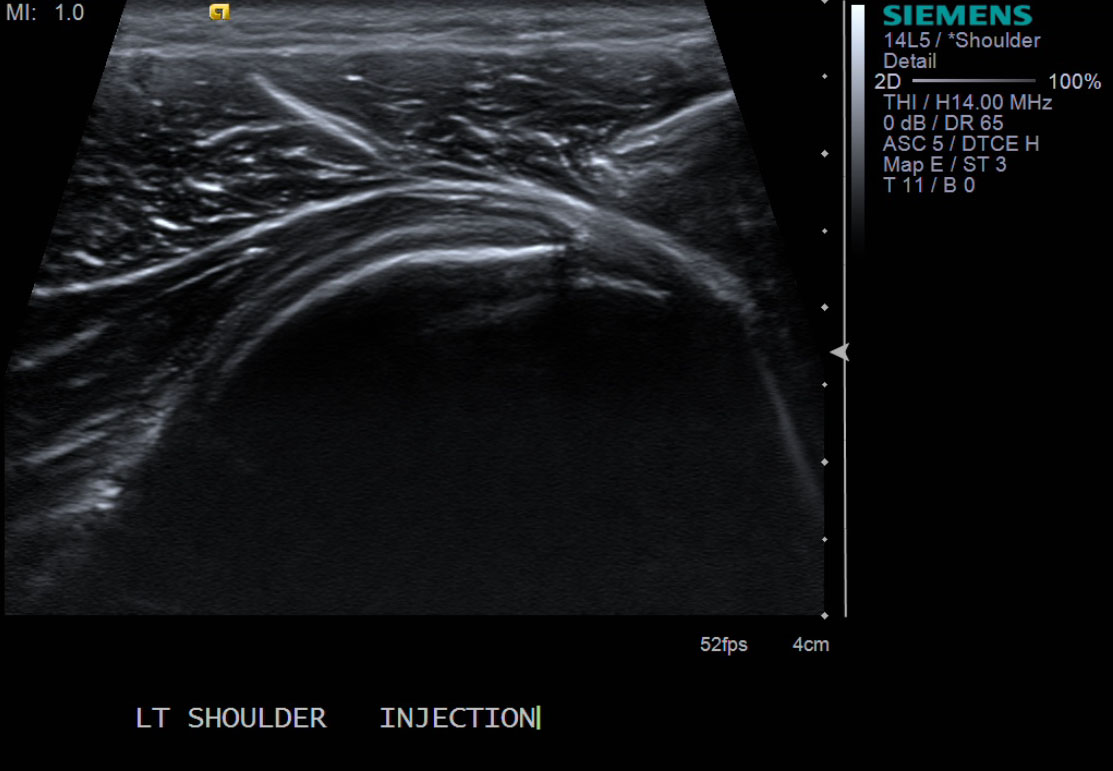

• descriptiondescription

• After advancing the needle to the level of the articular cartilage, there is easy flow of the injectate.